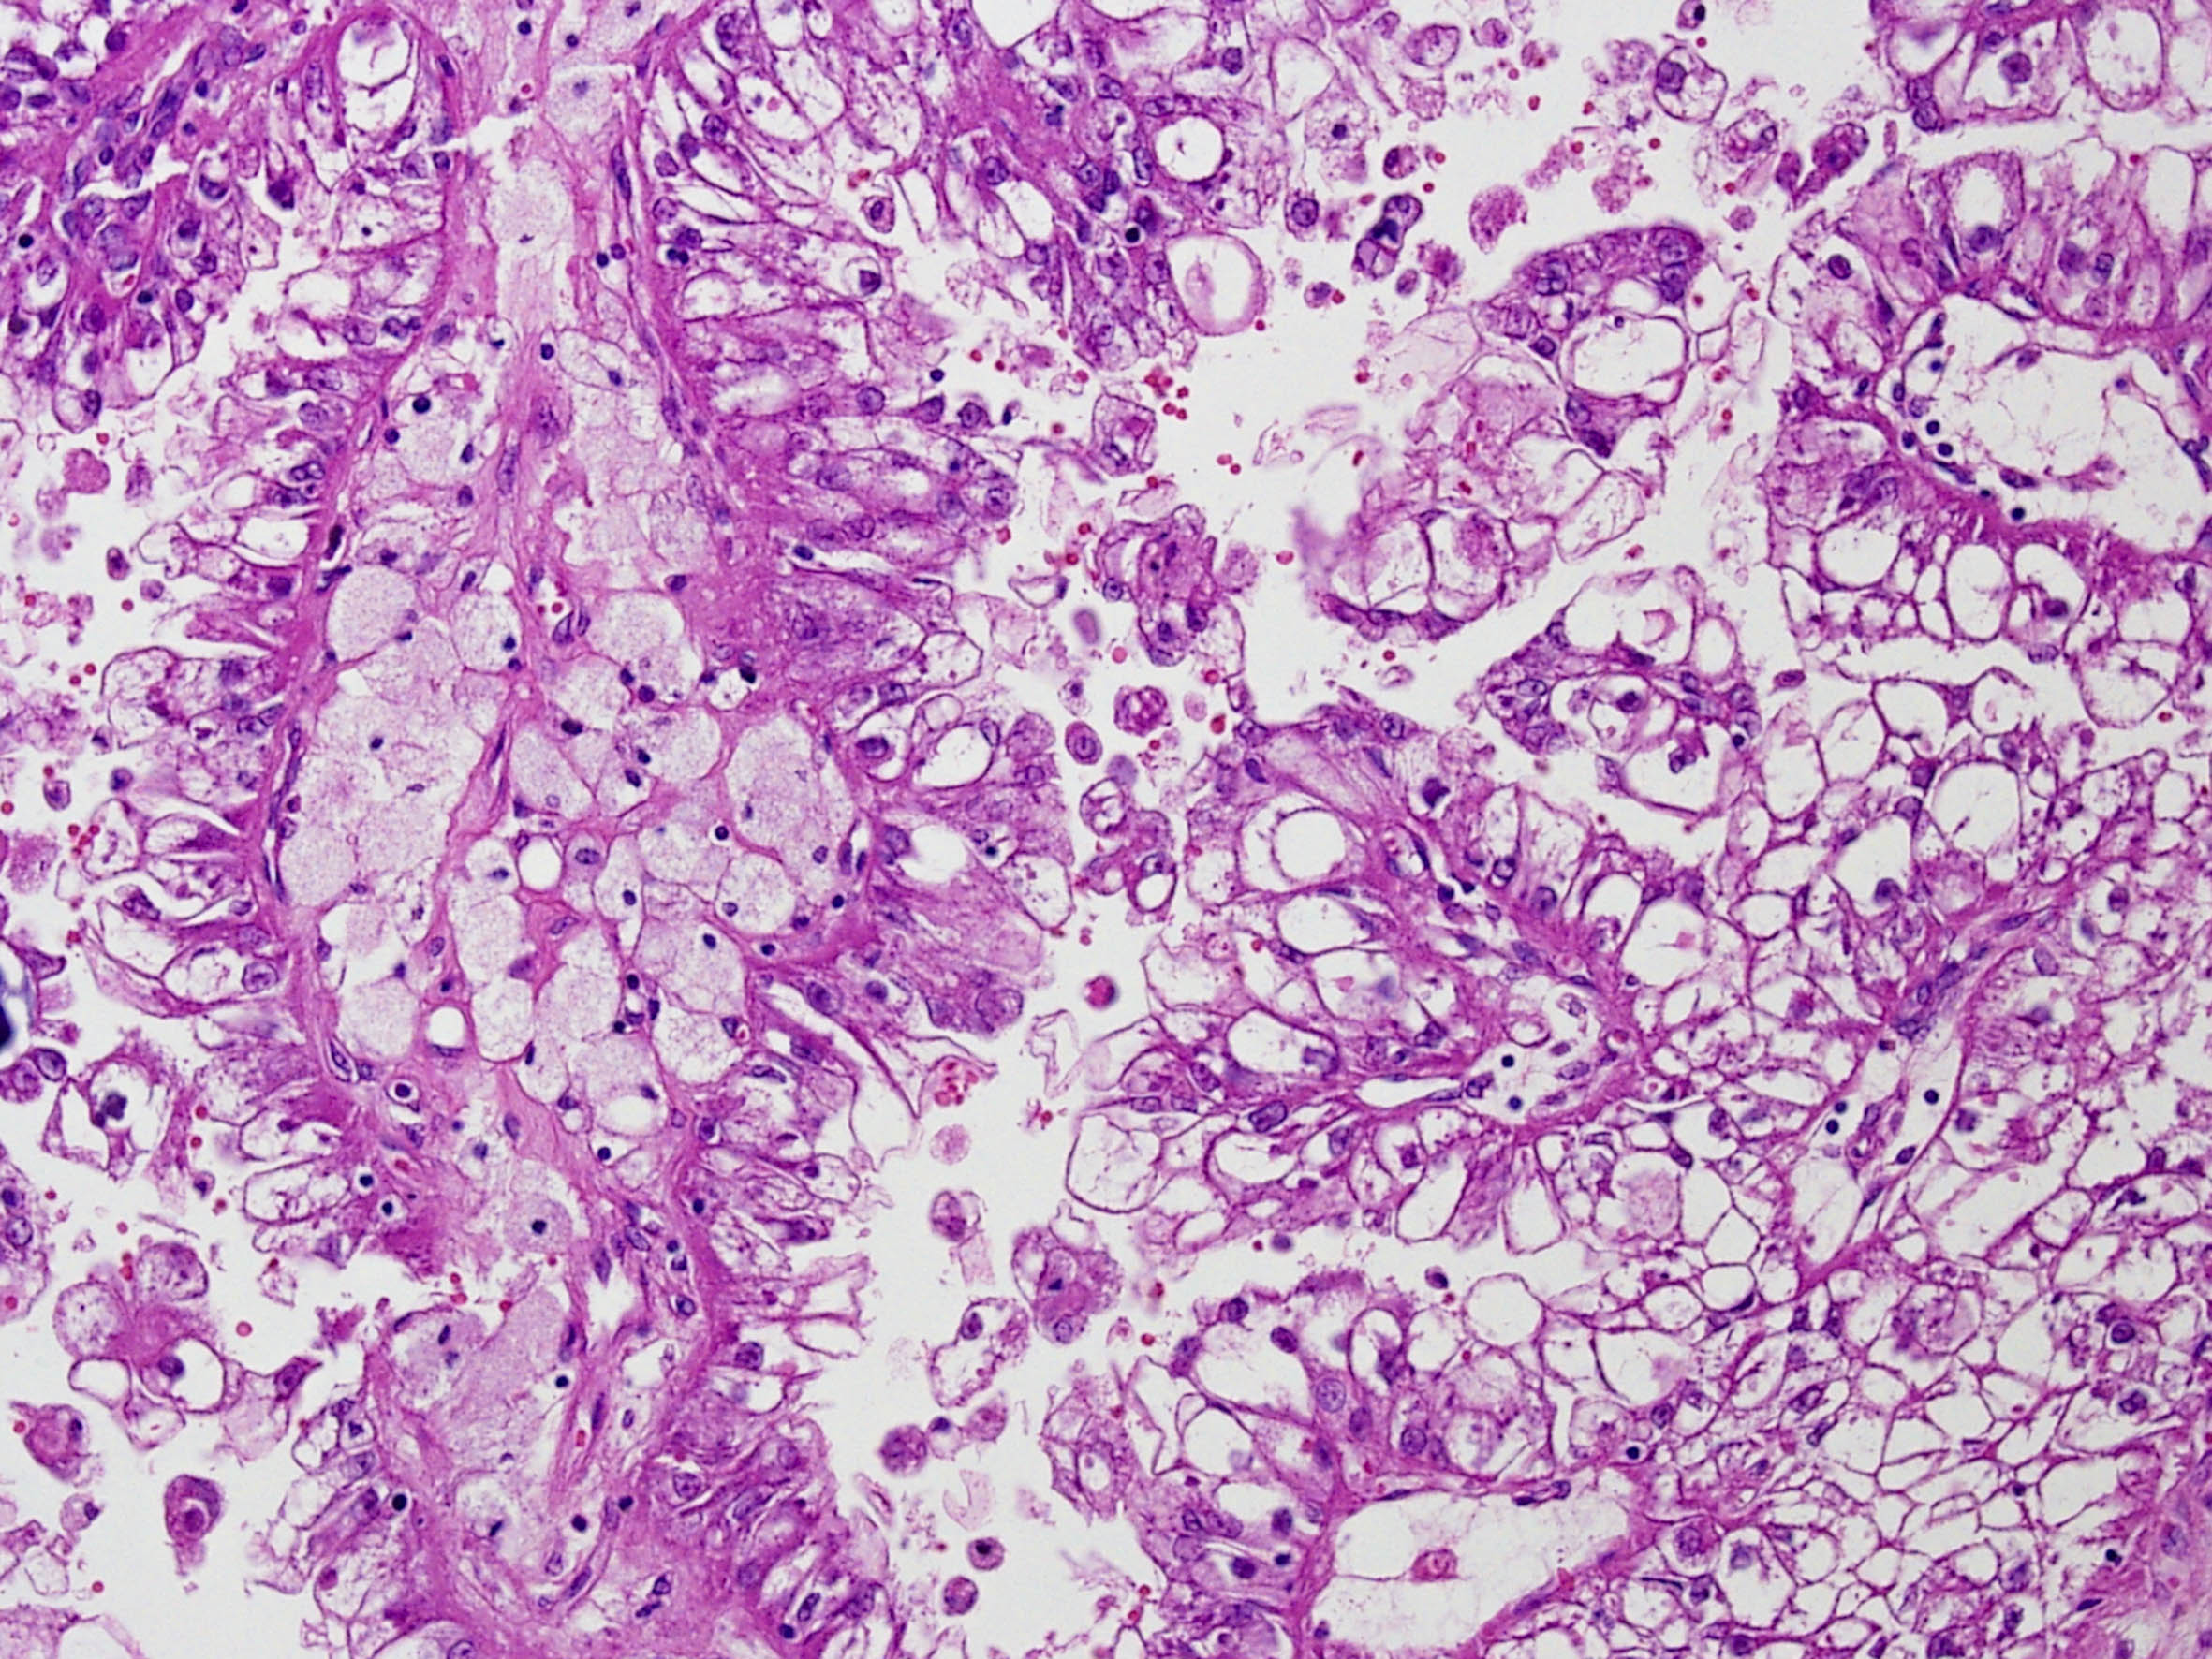

Classification of renal tumors

Case ID: 274